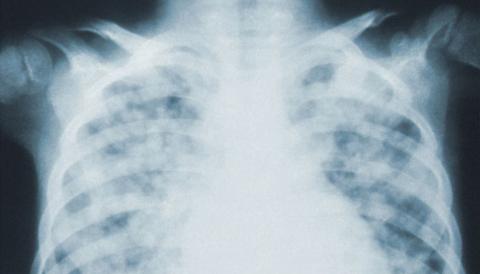

A University of British Columbia-led study has identified a computer technique that health facilities can use to screen, diagnose and monitor COVID-19 pneumonia more efficiently.

The researchers found that a pre-trained neural network called DarkNet-19 can rapidly and reliably detect COVID-19 on chest X-rays. The network recognized the disease’s imaging patterns on nearly 6,000 chest X-rays with 94 per cent accuracy, outperforming 16 other available networks.

“In the earliest stages of COVID-19, chest X-rays often appear normal to the naked eye,” says Savvas Nicolaou, the senior author of the study and the director of emergency and trauma imaging at Vancouver General Hospital. “But in the right clinical context, applying AI-augmented analysis to the same images may reveal the subtle presence of the disease.”